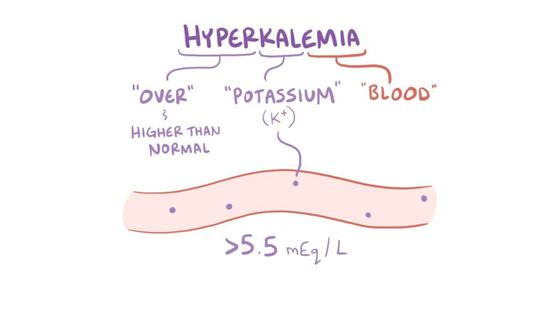

Entenda por que o excesso de potássio é uma emergência renal silenciosa e como prevenir.